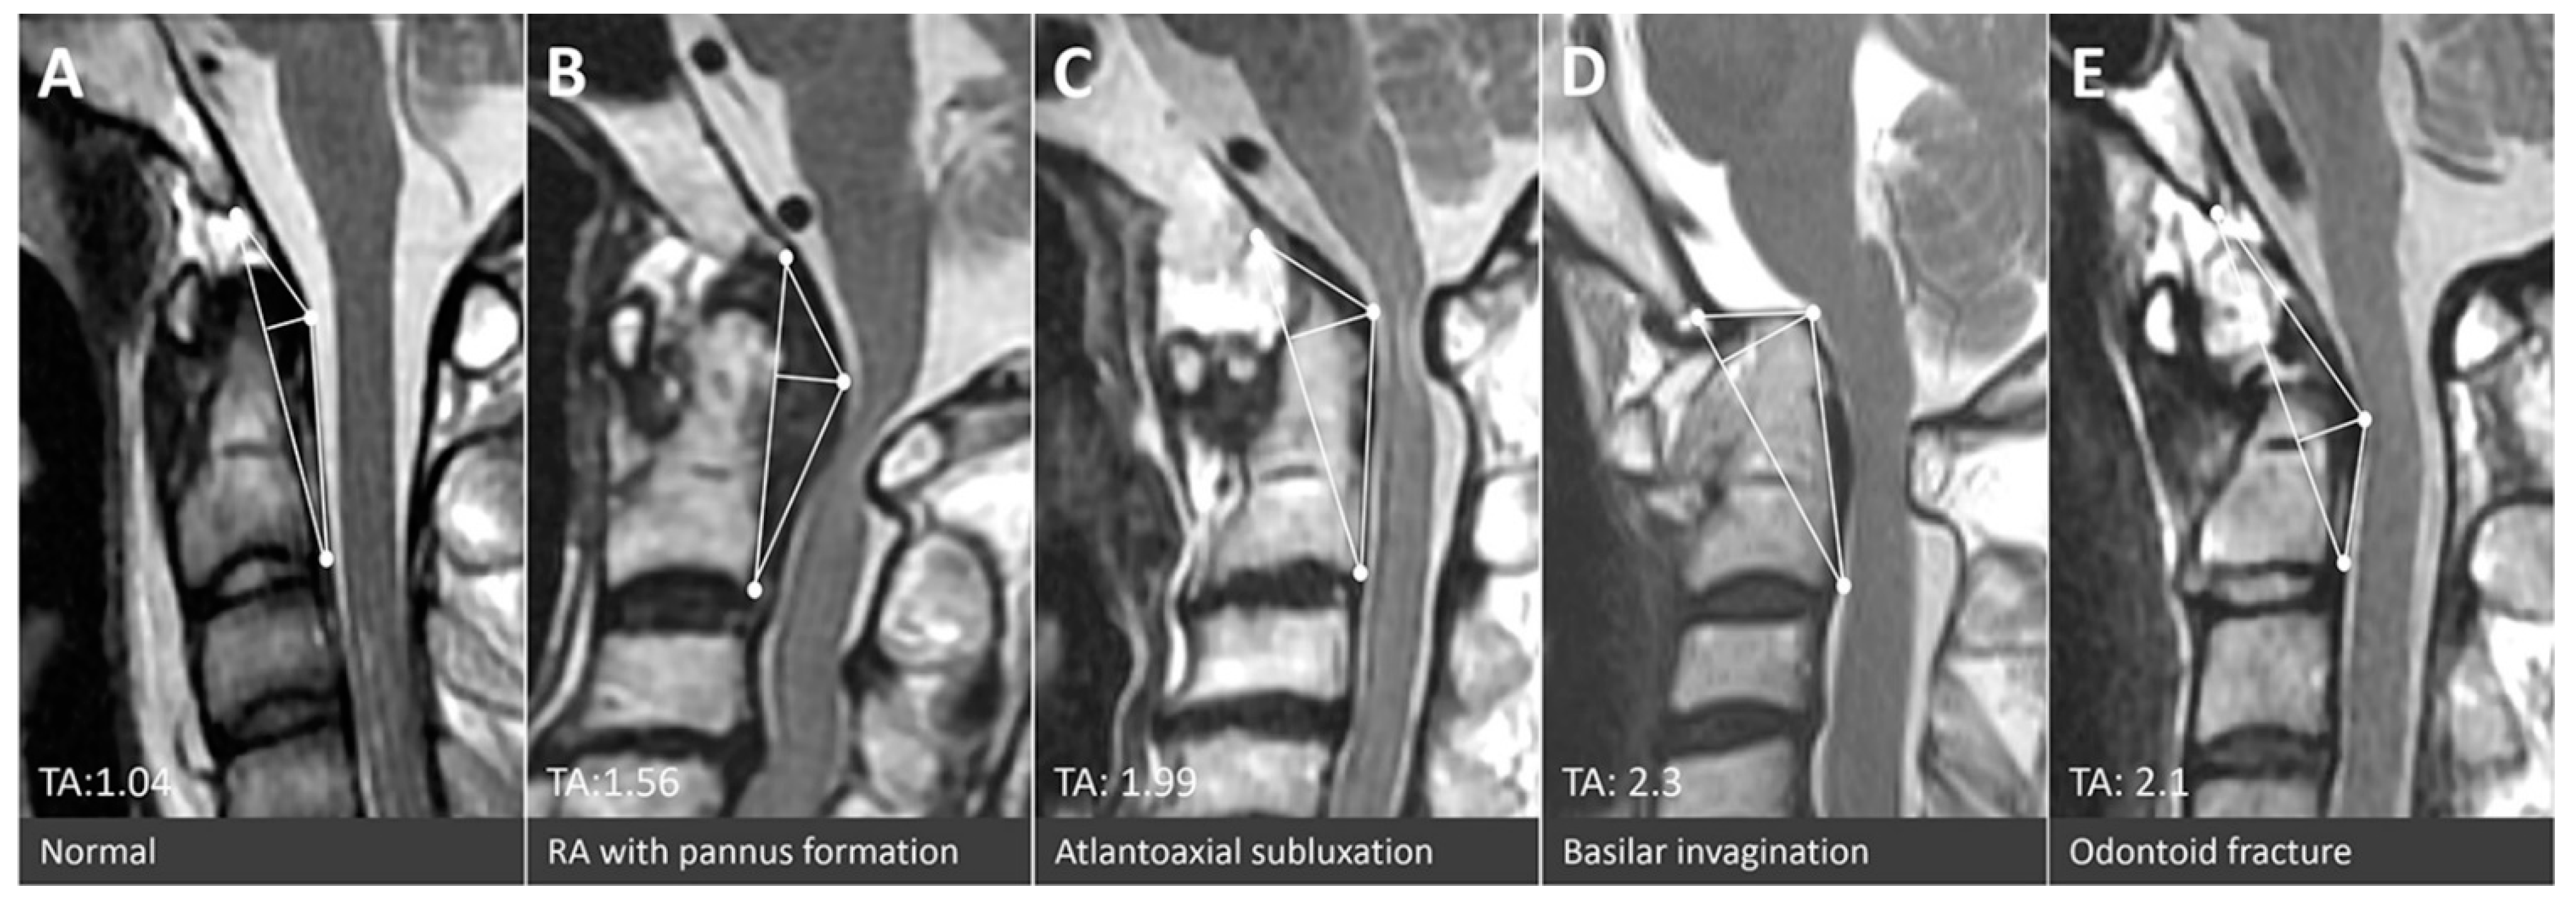

Figure 3.

Mid-sagittal T2 weighted magnetic resonance images of patients with (A) a normal CVJ, (B) rheumatoid arthritis with pannus formation, (C) atlantoaxial subluxation, (D) basilar invagination, and (E) odontoid fracture.

The authors advocate use of the TA of the CVJ as an intuitive and direct tool for quantification of compressive lesions on MRIs (Figure 3). The value of the TA is substantially based on two measurements: The base and the height of the designated triangle. The base, the longitudinal axis in normal CVJ anatomy, is mainly determined by the relative position between the skull-C1 complex and the C2 vertebrae. Thus, in circumstances of AA subluxation or odontoid fracture, the length of the base frequently increased and the TA would enlarge simultaneously (Figure 4C,E). The height is determined by the most dorsal indentation point in the ventral aspect of the medulla. Subsequently, the height is influenced by the thickness of the retro-odontoid soft tissues (Figure 4B) or the changes of cranio-medullary angle (Figure 4C,D). The ventral compression to the brain stem could be constantly represented by the simulated triangle in various kinds of CVJ pathologies. Animations of each type of CVJ pathologies and subsequently enlarged TAs are demonstrated in Figure 4. The animated categories of pathologies and deformities of the CVJ also could provide guidance to surgical strategies, which commonly combine decompression, reduction, and fixation.